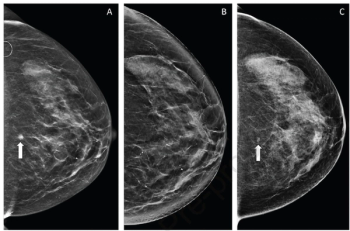

In a study of over 463,000 women who had screening mammography exams, adjunctive AI led to a 17.6 percent higher detection rate for breast cancer and a three percent increase in positive predictive value for recalls.

The combination of FDA-cleared AI software for mammography triage with a medical grade edge AI platform may allow the embedding of enhanced AI detection capability within existing mammography devices.

Noting significant variation with facilities for achieving passing criteria for mammography positioning, researchers found that structured interventions, ranging from weekly auditing of images taken by technologists to mechanisms for feedback from radiologists to technologists, led to significant improvements in a multicenter study.